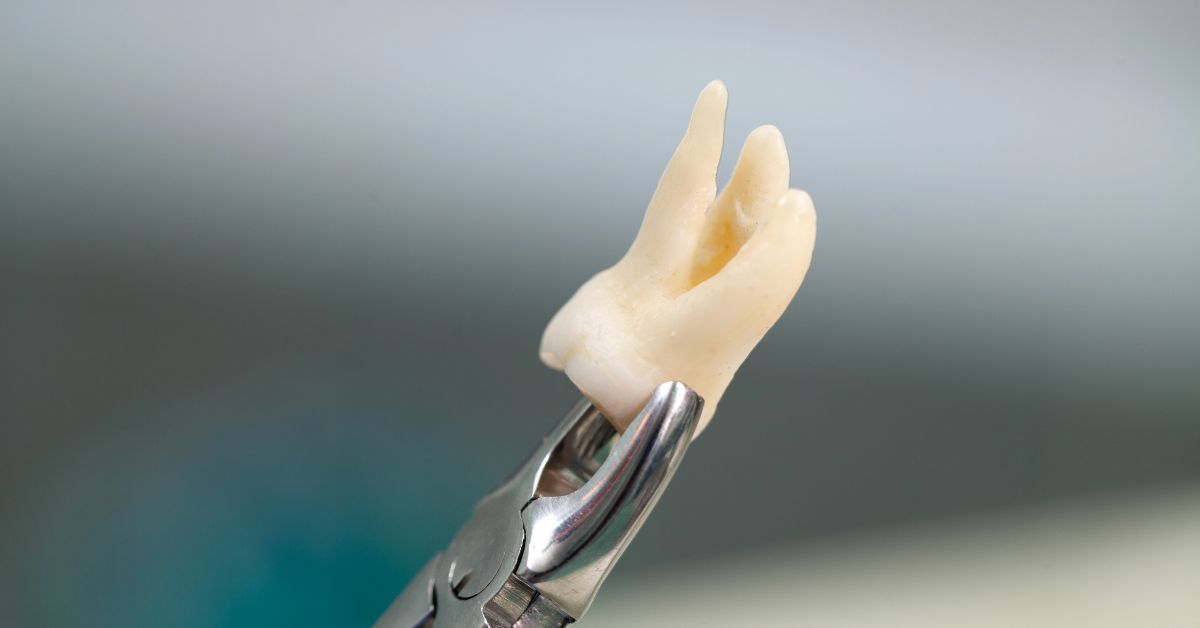

Wisdom Tooth Extractions in Los Angeles are often recommended when third molars threaten long-term stability, whether through impaction, repeated inflammation, pressure on adjacent teeth, or decay that becomes difficult to manage at the back of the mouth. Furthermore, wisdom teeth can create problems quietly, especially when they sit partially erupted or remain trapped under the gumline where bacteria collect and cleaning stays inconsistent. Removal focuses on preventing predictable complications, including infection episodes, damage to neighboring molars, and crowding pressure that can affect bite comfort over time. Patients often choose extraction when symptoms recur or when imaging shows the tooth position makes future problems likely.

PHD Dental approaches wisdom tooth removal with a planning-first mindset that prioritizes safe access, predictable healing, and a clear understanding of the tooth’s anatomy and eruption pattern. The team evaluates how each wisdom tooth sits relative to surrounding bone, soft tissue, and neighboring teeth so the treatment plan matches the complexity of the case. This clarity builds confidence because patients understand why extraction is recommended and what the procedure is designed to prevent. A well-managed outcome should reduce repeated flare-ups at the back of the mouth, protect adjacent teeth from long-term wear or decay, and support a smoother hygiene routine in a hard-to-reach area.

Third molars often erupt into limited space, and that crowding pressure can push on adjacent teeth or create a feeling of tightness in the back of the arch. While every mouth responds differently, impacted or partially erupted wisdom teeth can still add force and contact that complicates long-term alignment stability. Removing the wisdom teeth can reduce that back-of-arch pressure and help preserve the space relationships that support a more stable bite.

How Limited Space Creates Ongoing Force Against Adjacent Molars

When a wisdom tooth pushes into the second molar, the contact can create chronic pressure and make the area harder to keep stable. That pressure can also trap plaque and increase the risk of gum irritation between the teeth. Patients appreciate understanding that extraction can remove a constant mechanical stressor rather than waiting for the second molar to become compromised.